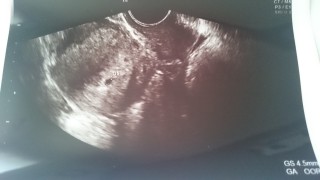

妊活3ヶ月。不妊検査を受けに病院へ行き、先生に『明日が排卵だよ』と言われて頑張りました(^^)造影剤の検査予約をしに病院へ行くため、念のために検査薬で調べたら陽性反応が。先生『まだ何もしてないのにね』って笑ってました。

まだ4週くらいだから見えるか分からないけど~と言われ不安に思いながら内診。まだまだ4,5mmの小さな袋ですがしっかり見えてくれました!科学流産乗り越えてやっときてくれた小さな命。大事に育てていきたいと思います。